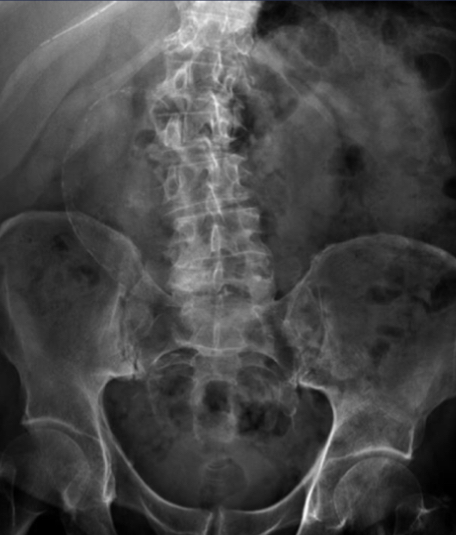

What is this abdominal x-ray showing?